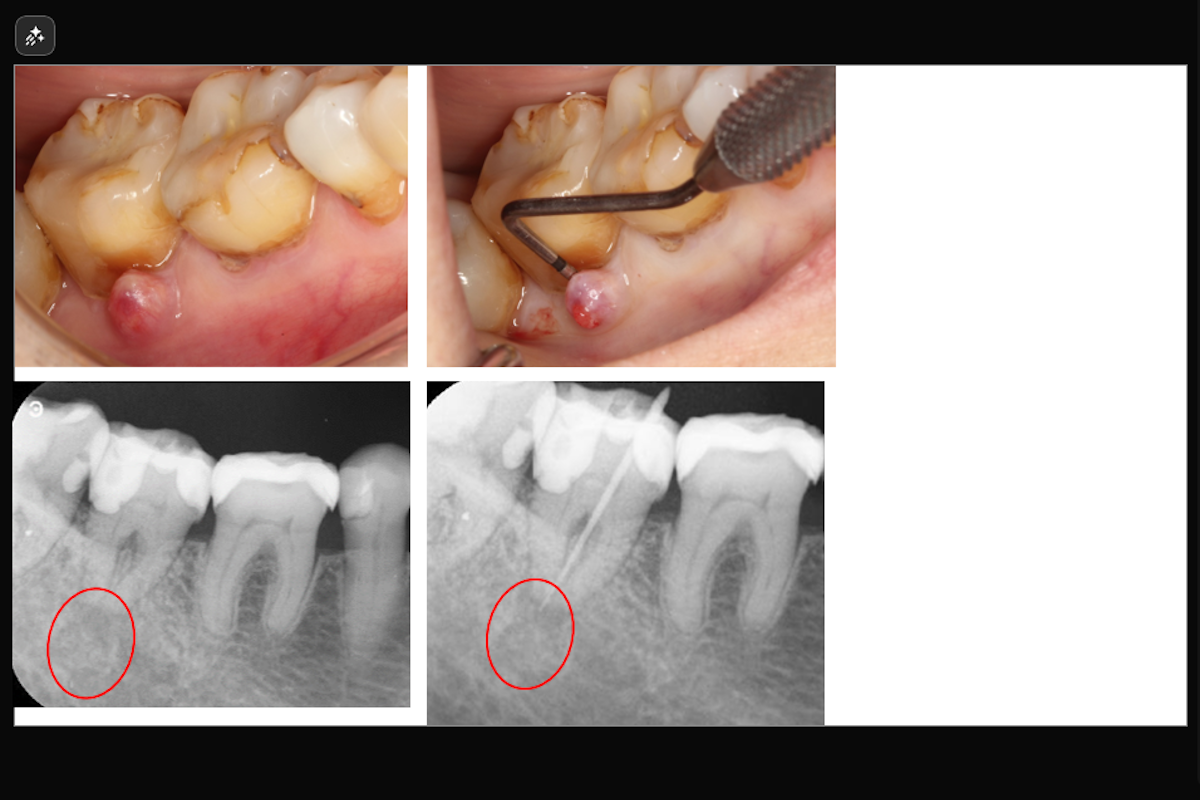

【二重に彎曲した樋状根の症例】「歯茎を押すと膿が出て痛い、他院で歯周病の治療を約1年続けていたが腫れが引かない。」

「歯茎を押すと膿が出て痛い、他院で歯周病の治療を約1年続けていたが腫れが引かない。」ということで来院された患者様の症例です。

- 主訴:歯茎を押すと膿が出て痛い、他院で歯周病の治療を約1年続けていたが腫れが引かない。

- 治療内容: 下顎右側第二大臼歯

- 根管治療(レーザーを用いた根管洗浄)